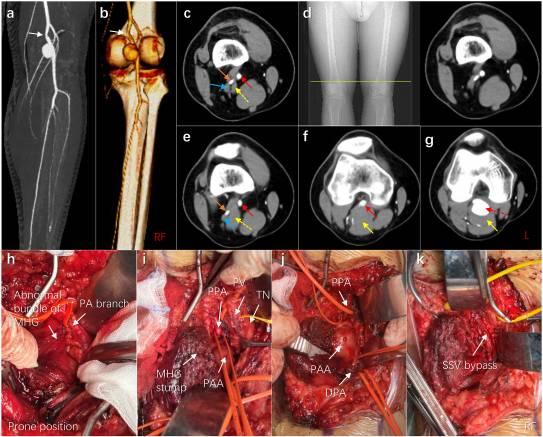

初步诊断考虑PAES,对增强CT图像进行了重新评估,显示腓肠肌(MHGM)内侧头的部分肌束穿过PA和腘静脉(PV)之间的PA外侧(图1c-eg)。这种异常的肌束起源于股骨内侧髁上方,高于正常的MHGM起源(图1d)。因此,这是III型PAES的典型病例。推测异常的MHGM会导致PA长期受压,引发PA壁微创,进而导致假性动脉瘤的形成。

图1 PAES患者在诊断和治疗过程中的图像。(a,b)计算机断层血管造影(CTA)显示的右腘动脉(PA)动脉瘤。PA狭窄用白色箭头表示。(c-g)轴位图像显示异常肌束和腘动脉瘤(PAA)。d中的黄线显示了该肌束起源于股骨内侧髁上方的位置。红色箭头表示PA。黄色箭头表示腓肠肌(MHGM)的内侧头,其中虚线表示异常的肌束。橙色箭头显示PA的分支。蓝色箭头显示腘静脉(PV)。(h-k)术中照片显示MHG、近端PA(PPA)、远端PA(DPA)、PV、胫神经(TN)和小隐静脉(SSV)的异常束

对患者进行手术治疗。在全身麻醉并俯卧后,在右腘窝做了一个S形切口,并进行了分层解剖,以暴露胫神经(TN)、PV和PA。部分MHGM肌束在PA分支下方延伸,终止于股骨内侧髁(图1h)。完全切断MHGM并暴露PAA(直径约3.5 cm),以完全暴露PA的近端和动脉瘤(图1i和j)。暴露动脉瘤后,观察到大量陈旧的附壁血栓。收集动脉瘤组织进行病理检查。由于PA远端段逆行血流不良,使用3-French血栓切除导管进行了两次血栓切除术。最后,通过健康动脉的端到端吻合,成功进行了反向SSV(小隐静脉)旁路移植(图1k)。